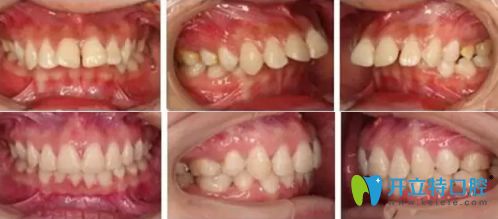

這個(gè)19歲姑娘矯正上下牙齒擁擠中線不齊,只用了一年半時(shí)間

你知道19歲矯正牙齒要多久嗎?這個(gè)19歲的小姐姐在廣州廣大口腔矯正牙齒擁擠不齊,只用了一年多的時(shí)間哈。